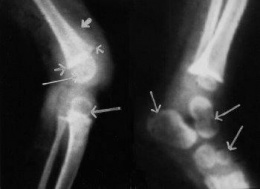

Las lesiones corresponden al engrosamiento irregular y difuso de las diáfisis de los huesos largos; fragilidad de los huesos, incluso pueden cortarse en rebanadas con un cuchillo; son frecuentes las deformaciones esquelétricas; puede haber lordosis o sifosis; en ocaciones puede observarse separaciones de la cabeza del fémur de la cápsula articular; la médula ósea está roja y llena de petequias.

- Fractura de huesos.